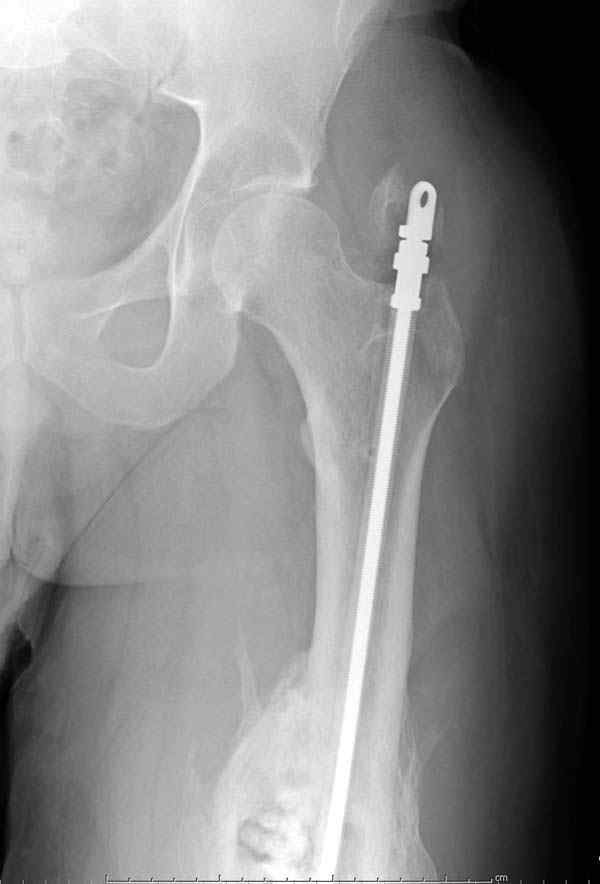

Через 4,5 лет после травмы выявлены рентгенологические признаки консолидации перелома, признаки хронического остеомиелита купировались. Аппарат был демонтирован. Пациент продолжил ходьбу с дозированной нагрузкой на конечность при помощи костылей. Через 2 месяца начал ходить при помощи трости. Однако, еще через 2 месяца отметил появление свищей на бедре с гнойным отделяемым и укорочение длины конечности. При осмотре в январе 2007 г.: пациент ходит при помощи костылей без опоры на левую нижнюю конечность, на бедре имеются множественные рубцы, на наружной поверхности сегмента в верхней и нижней третях имеются два свищевых хода со скудным серозно-гнойным отделяемым; отечности тканей конечности нет, пальпация безболезненная, отмечается укорочение длины конечности на 5 см, патологическая подвижность не определяется, имеется стойкая разгибательная контрактура коленного сустава (разгибание - 180 гр, сгибание - 170 гр), признаков нарушения кровоснабжения и иннервации тканей конечности нет. Температура тела нормальная. В общих анализах крови и мочи отклонений от нормы нет. [image 06,07, 08 (стрелками отмечены свищевые раны, 09, 10]Дорогие коллеги, я уверен, что у многих из вас после знакомства с данным клиническим наблюдением появится множество вопросов, касающихся уже проведенного лечения (особенно, сроков и способов). Сразу оговорюсь - я не смогу правильно ответить на многие вопросы (особенно касающиеся предшествующего периода лечения). Прошу вас, конечно по возможности, сосредоточить внимание не на разборе допущенных ошибок (проведенного лечения), а помочь добрым советом относительно тактики наших дальнейших действий. Наверное, кто-то располагает бесценным опытом лечения подобной патологии.

Первым этапом мы планируем наложить спице-стержневой аппарат на бедро. После операции устраним углообразную деформацию и небольшое смещение по ширине. Затем постараемся выполнить дистракцию для восстановления длины конечности. А вот потом очень заманчиво поставить в костномозговой канал спейсер с антибиотиками и в последствие - интрамедуллярный блокируемый штифт.